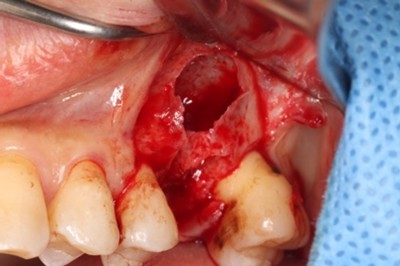

抜歯およびRidge Preservation時の口腔内写真

抜歯時に頬側の骨の大きな欠損を認めた。サイトランス®を使用したRidge Preservation、Cytoplast®※を使用し抜歯窩を被覆

骨の再生が起きており十分な骨幅を認める

破折歯を抜歯した場合、今回のケースのように骨の吸収が著しく生じていることが多く、このままではインプラント周囲に十分な骨幅(理想的にはプラットフォームから2mmの骨幅)を維持することができないためRidge Preservationは非常に有効な手法であると考える。